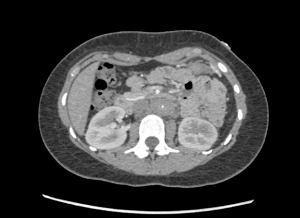

Patient underwent CT angiogram of her chest and abdomen emergently and the findings were suspicious for “periaortitis in association with midaortic syndrome with severe stenosis/near occlusion of the infrarenal aorta, bilateral renal arteries, celiac trunk, and SMA.” Findings that could represent a vasculitis versus neoplastic process.

Aorta computed tomography

Occluded aorta